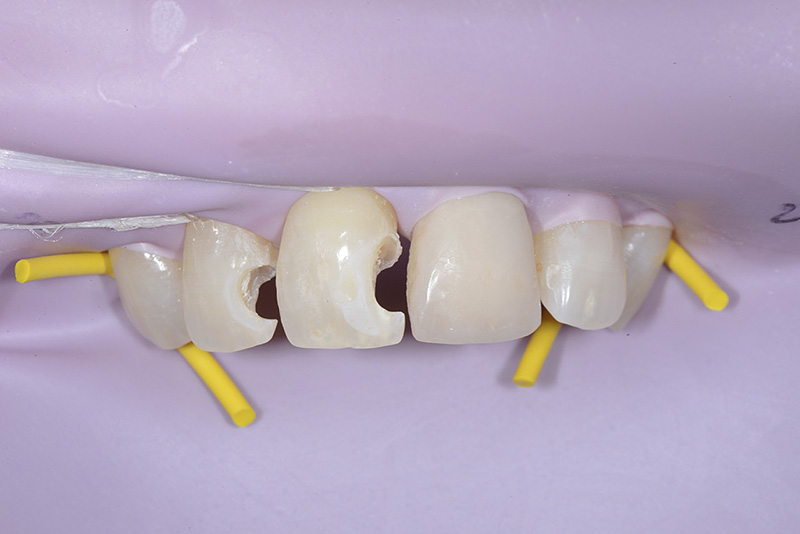

Vengono utilizzati 2 tipi di provvisori: il primo, cementato ai denti vicini, viene utilizzato dal momento dell’estrazione del dente fino ad impianto osteointegrato (circa 6 mesi); il secondo, avvitato direttamente all’impianto, ha una funzione di prova estetica ma soprattutto di guida per la maturazione dei tessuti gengivali peri-implantari portandoli verso la maturazione completa prima di posizionare la corona finale in disilicato di litio.